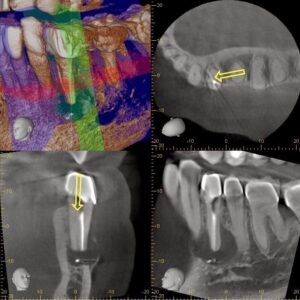

Our exam found #21 normal to percussion, normal probings and swelling on the buccal. An additional canal was suspected, so CBCT was taken for further review.

CBCT clearly shows an additional lingual canal. CBCT mapping allowed us to determine where the canal would be located and confirm that it had its own apical foramen. With greater understanding of the canal anatomy, available only through 3D imaging, we recommended non-surgical retreatment to address the missed lingual canal.

With the aid of the microscope, we were able to locate and treat the missed lingual canal.